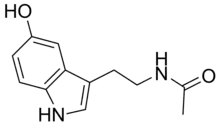

| N-Acetylserotonin | Animals | 5-OH | H | O=C-CH3 | 5-hydroxy-N-acetyltryptamine | 1210-83-9 |